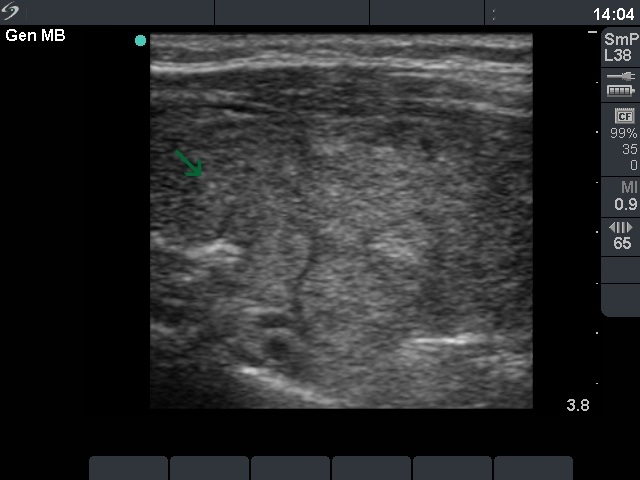

Ultrasonography: a moderately hypoechogenic thyroid was found with multiple circumscribed lesions divided by fibrous tissue. One of these areas contained hyperechogenic granules and exhibited increased vascularization.

The US pattern of this patient highly resembles that of the so-called micronodular form of Hashimoto's thyroiditis. The "nodules" in this case are in truth pseudolobules of the lobes. The prominent appearance of the fibrous tissue dividing the lobules resembles a capsule of a follicular adenoma. In contrast with the latter, not only one or two, but numerous circumscribed areas are present in this case.